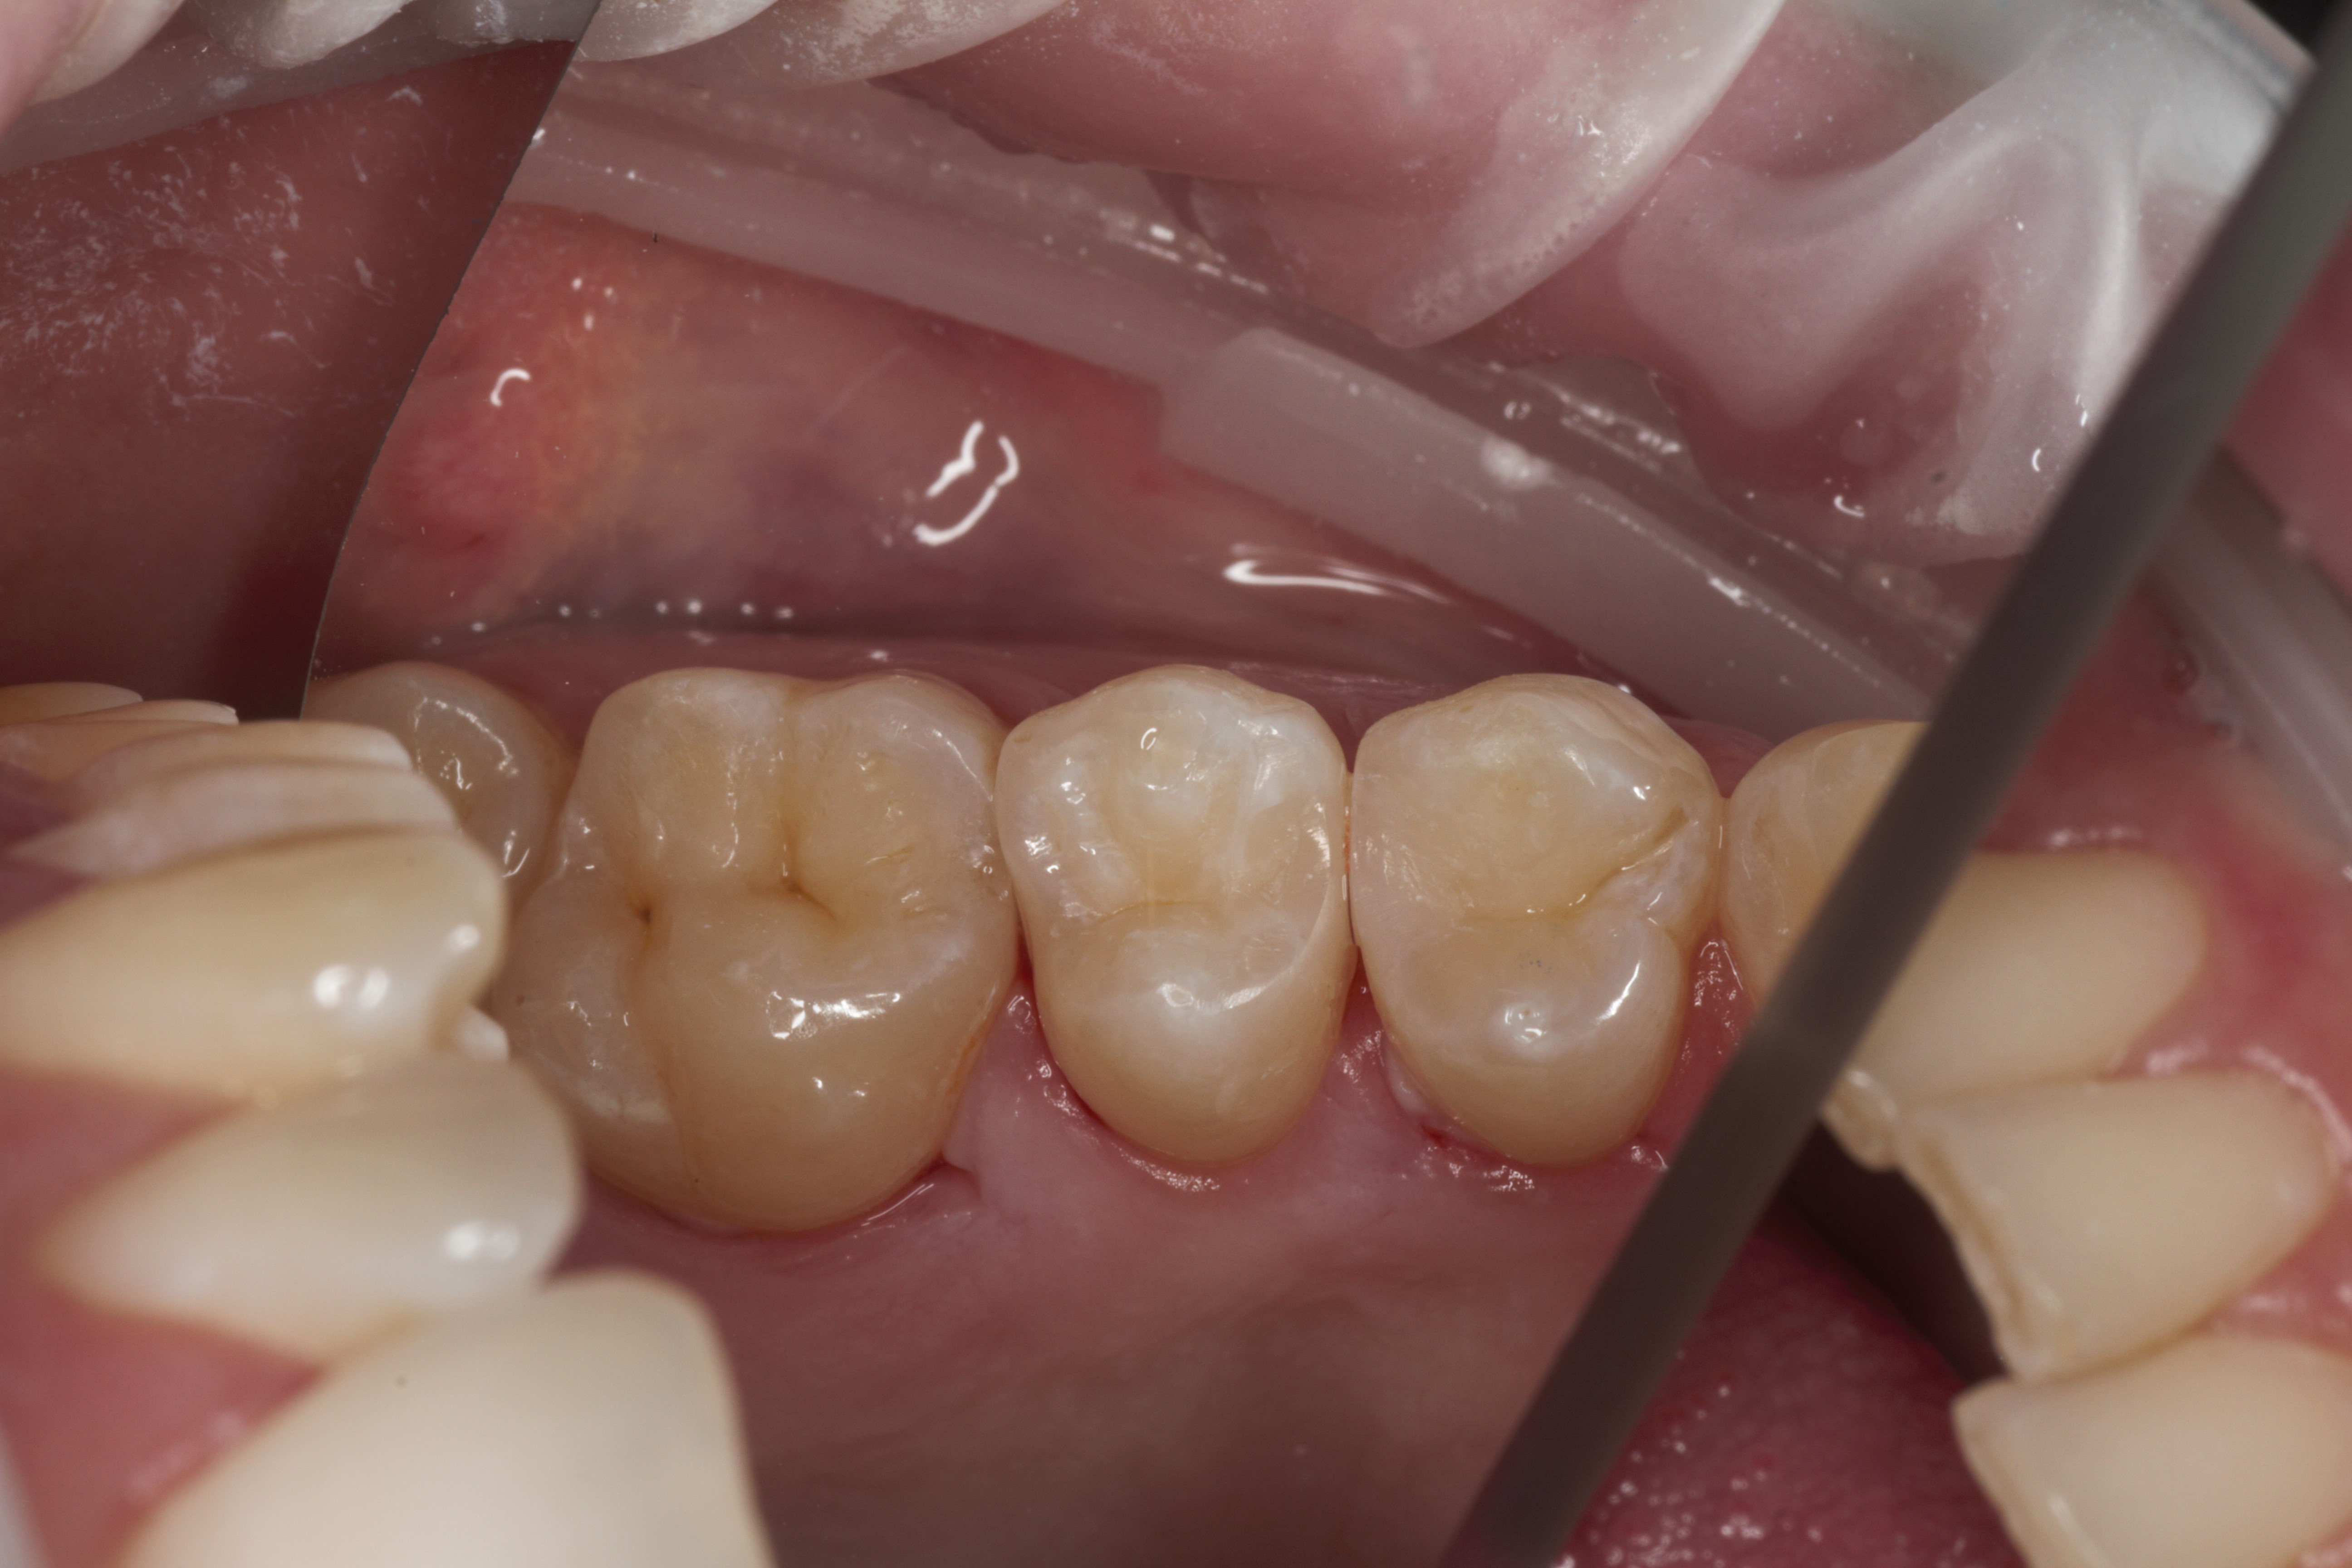

- Эстетическая реставрации жевательной и фронтальной группы зубов современными пломбировочными материалами, диагностика кариеса на ранних этапах развития, предупреждение образования вторичного кариеса в области запломбированных зубов

- Подготовка зубов к ортопедическому и ортодонтическому лечению, с учетом назначенного плана лечения